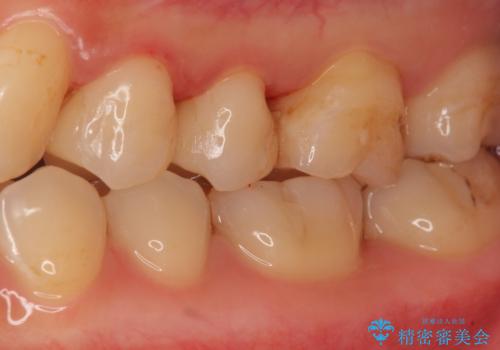

セラミックインレーによる治療

- 銀の詰め物を白くしたいとのことで来院。

銀の詰め物を除去した後、う蝕が残っていないかを拡大鏡下で確認し

セラミックの詰め物(e-maxインレー)にて治療を行いました。

- e-maxインレー 7.7万円 ×2本費用は治療当時の料金となります